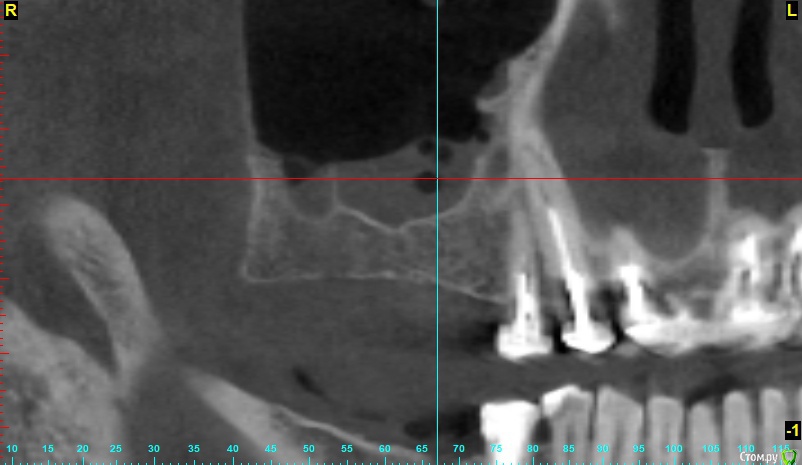

x4ex Опубликовано 7 ноября, 2018 Поделиться Опубликовано 7 ноября, 2018 Добрый день, коллеги! Планируется синус-лифт справа, по словам пациент ЛОР сказал, что противопоказаний не видит. Якобы есть полипы, которые он может убрать эндоскопически, но смысла в этом не видит, потому как со временем они вырастут снова. Но мне картина на КТ похожа не на полипы, а на жидкость с пузырьками воздуха. Кто что думает, стали бы синусить? Ссылка на комментарий

Тимур86 Опубликовано 7 ноября, 2018 Поделиться Опубликовано 7 ноября, 2018 (изменено) я бы 3 коротких поставил. слизистая не гипертрофирована по стенкам-соустье должно открытым быть!ОРВИ во время снимка не было? Изменено 7 ноября, 2018 пользователем Тимур86 1 Ссылка на комментарий

x4ex Опубликовано 7 ноября, 2018 Автор Поделиться Опубликовано 7 ноября, 2018 я бы 3 коротких поставил. слизистая не гипертрофирована по стенкам-соустье должно открытым быть!ОРВИ во время снимка не было? не вижу соустья. ОРВИ говорит не было, на прошлом снимке год назад ещё хуже. Ссылка на комментарий

___49___ Опубликовано 12 ноября, 2018 Поделиться Опубликовано 12 ноября, 2018 (изменено) У пациента , фронтит, гайморит двусторонний и этмоидит в стадии ремиссии (сопли) скорее всего , проблемы чисто ЛОРа . Лучше решать вопрос без задействования синуса ИМХО. Изменено 12 ноября, 2018 пользователем ___49___ Ссылка на комментарий